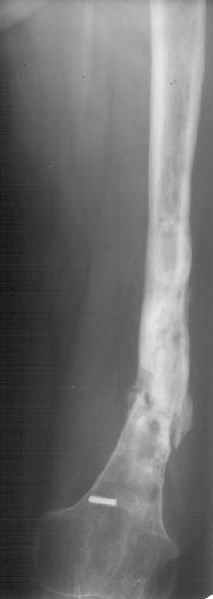

К нам поступила худощавая женщина 48 лет, которой года 2,5 назад был выполнен остеосинтез бедра пластинкой в одной из горбольниц. В сентябре 2001 г. пластинку убрали. Начала разрабатывать движения, ходила с тростью. С января этого года

отмечает усугубление деформации бедра и улучшение движений "в коленном суставе". При осмотре имеетсяподвижность на месте перелома (псевдартроза), больше в сагиттальной плоскости. Рентгенограммы в приложении(фас; профиль). Полностью угол, открытый кзади, под нагрузкой не устраняется. "Сгибается" еще градусов на 30. Ходит с тростью. Надколенник неподвижен, в суставе, видимо, движений нет совсем. В любом случае надо, видимо, начинать с восстановления оси и стабилизации бедра. Как окончательный фиксатор хотелось бы использовать интрамедуллярный стержень. Можно ли в данном случае устранить угол одномоментно? Или лучше дозированно? Нужна ли костная пластика местно? Не стоит ли пойти на мобилизующую операцию в один этап? Если да, то какую?Может быть, есть еще какие-то моменты, которые следует учесть?Спасибо заранее.-- Best regards, Alexander N. Chelnokov

The pt has 20 degree of varus and 30-40 degree of procurvatum Acute correction may compromise the nurovascualr structures. Moreover xray shows evidence of infection and she has almost knee range of motion.

Не сформировалось у нас убежденности в целесообразности мобилизующей операции в один этап с остеосинтезом. Решили пойти по максимально щадящему пути. Первым этапом наложили аппарат. Снимок (см. приложение) сделан в положении максимально возможной коррекции оси, достигаемой одномоментно исправлением "об коленку" с ручным растягиванием колец сзади. Варус удалось убрать, а вот антекурвацию, от греха, лучше устраним дозированно, дней за 7-10. Потом планируем антеградный закрытый интрамедуллярный остесинтез. Буду признателен за отклик.